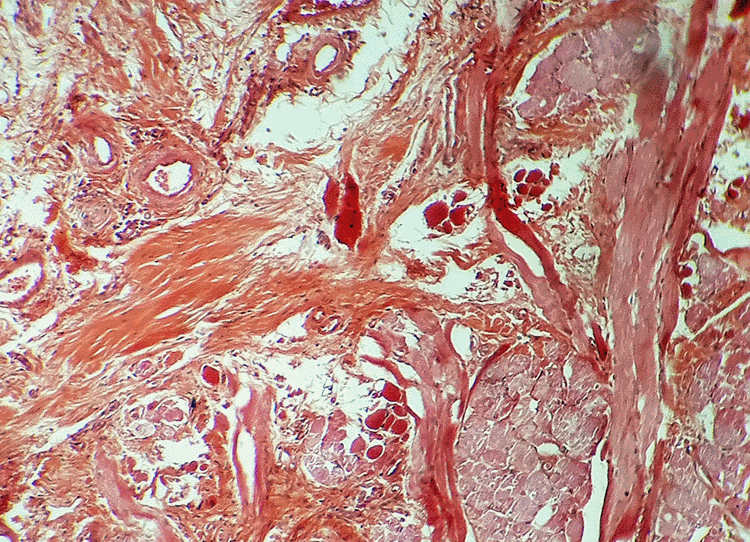

Aujourd'hui, le coffret renferme une collection de coupes histologiques réalisées en 1926 à l'Hôpital Saint Michel à Paris. Nous avons photographié quelques-unes de ces lames portant les fines tranches de tissus biologiques humains préparées à partir de prélèvements sur des patients. Nous ne sommes pas à même de reconnaître les zones médicalement intéressantes et, pour les photographies, nous avons privilégié le jeu des formes et des couleurs : c'est une façon de remarquer la qualité des préparations presque centenaires. Le microscope que nous avons utilisé est plus actuel que l'élégant "Nachet à pied anglais" recommandé, autrefois, pour les travaux d'histologie et de bactériologie. |

| Estomac (Dr V. Pauchet - 1926) | Rectum (Dr R. Duval - 1926) | ||||||||||||||||||||||||||||||||||||||||||||||||||||||||||||||||||||||||||||||||||||||||||||||||||||||||||||||||||||||||||||||||||||||||||||||||||||||||||||||||||||||||||||||||||||||||||||||||||||||||||||||||||||||||||||||||||||||||||||||||||||||||||||||||||||||||||||||||||||||||||||||||||||||||||||||||||||||||||||||||||||||||||||||||

| 3 mai 1926 - Estomac - Dr Pauchet, St Michel | |||||||||||||||||||||||||||||||||||||||||||||||||||||||||||||||||||||||||||||||||||||||||||||||||||||||||||||||||||||||||||||||||||||||||||||||||||||||||||||||||||||||||||||||||||||||||||||||||||||||||||||||||||||||||||||||||||||||||||||||||||||||||||||||||||||||||||||||||||||||||||||||||||||||||||||||||||||||||||||||||||||||||||||||||